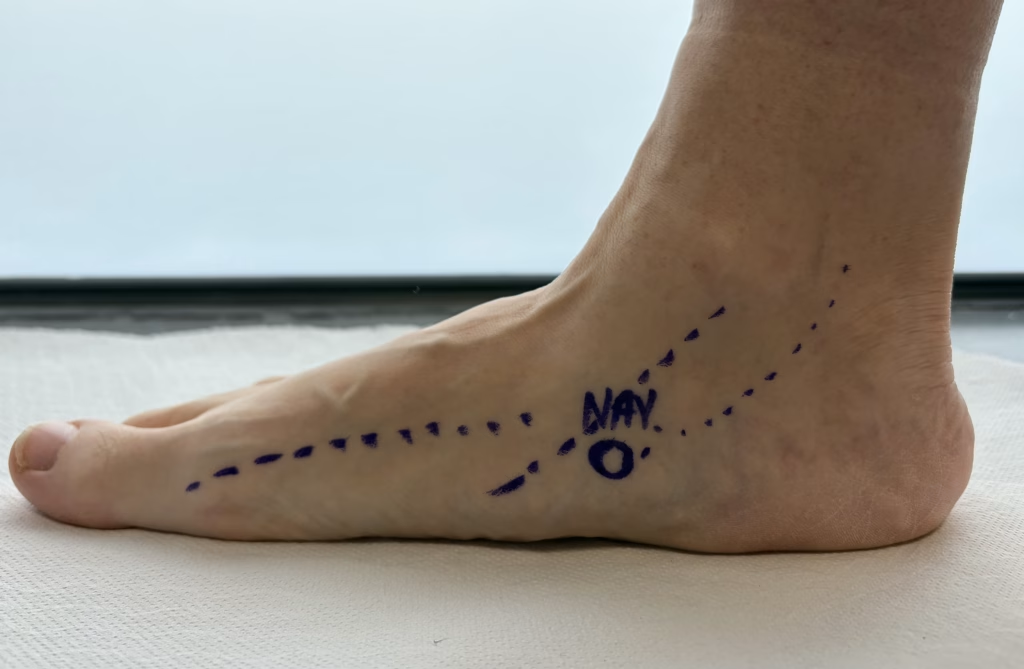

Your surgical plan depends on whether the foot is flexible or rigid, tendon integrity, joint condition, and severity of collapse. Options may include:

A detailed consultation and weight-bearing imaging help determine which combination is most appropriate for your foot.

Assessment typically includes a clinical examination, gait assessment, and weight-bearing X-rays. Depending on your symptoms, an ultrasound or MRI may be used to assess tendon and ligament condition.